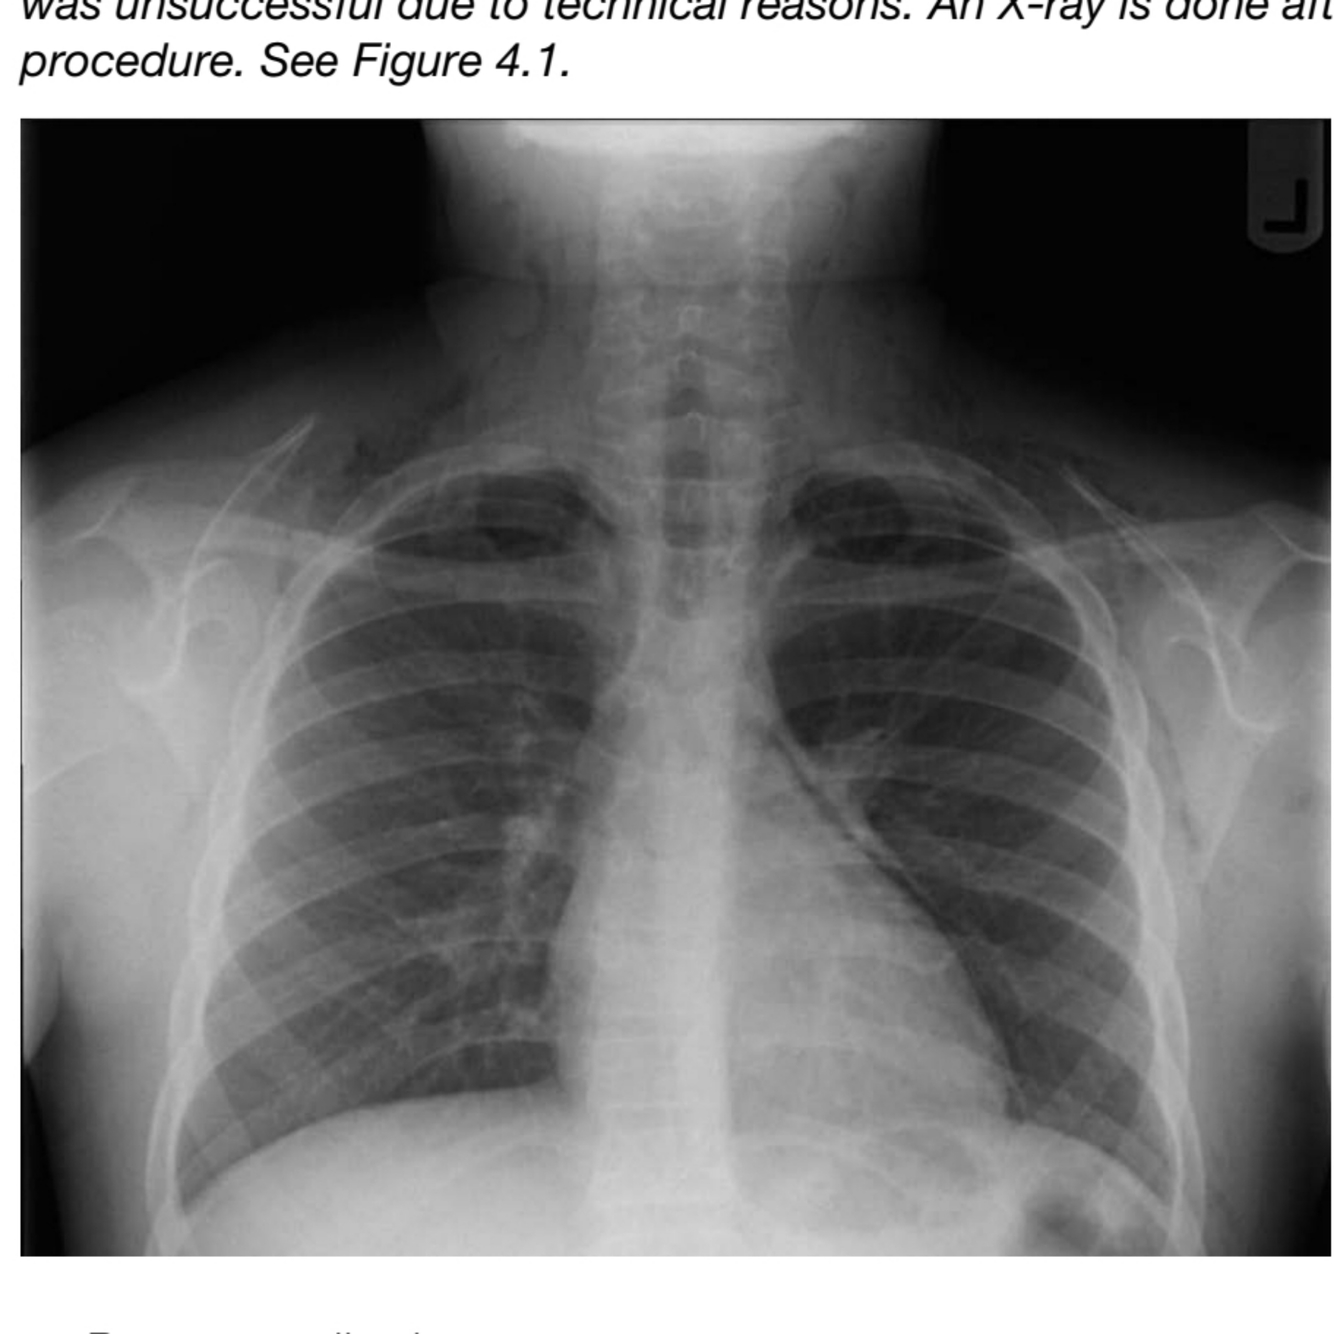

The ICU team has tried to do an early percutaneous tracheostomy, which

was unsuccessful due to technical reasons. An X-ray is done after the

procedure. See Figure 4.1

comment on the chest X-ray

A

• Pneumomediastinum

Cause of pneumomediastinum: Traumatic intubation or tracheostomy/NG

insertion as children have fragile soft tissue in trachea and oesophagus